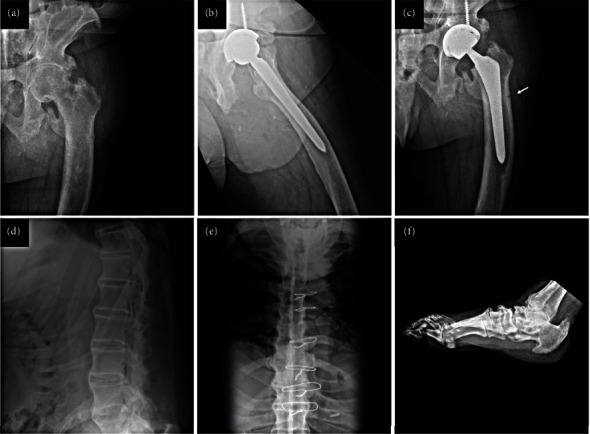

Abstract Image